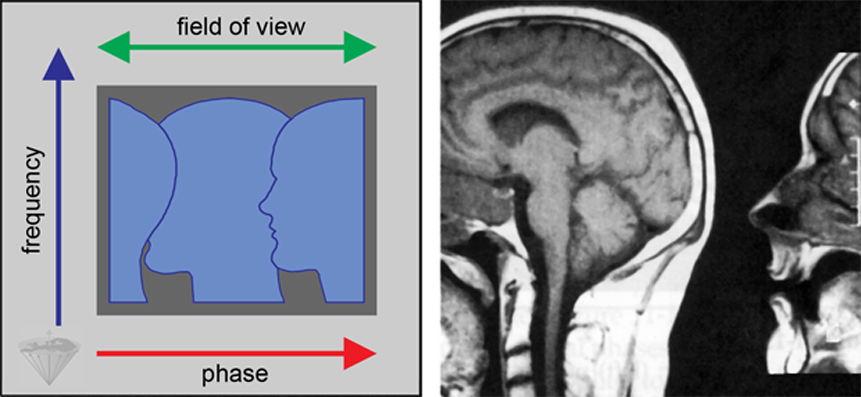

Figure 17-15:

Backfolding artifact resulting from the sample being larger than the field of view in the phase en­­cod­­ing di­rec­tion, which is orientated left-right in this example.